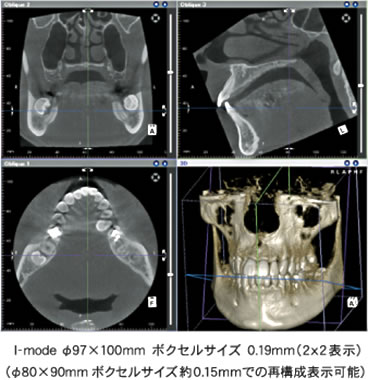

浜松市の井口歯科では 最新鋭の歯科用ctレントゲンを導入しています